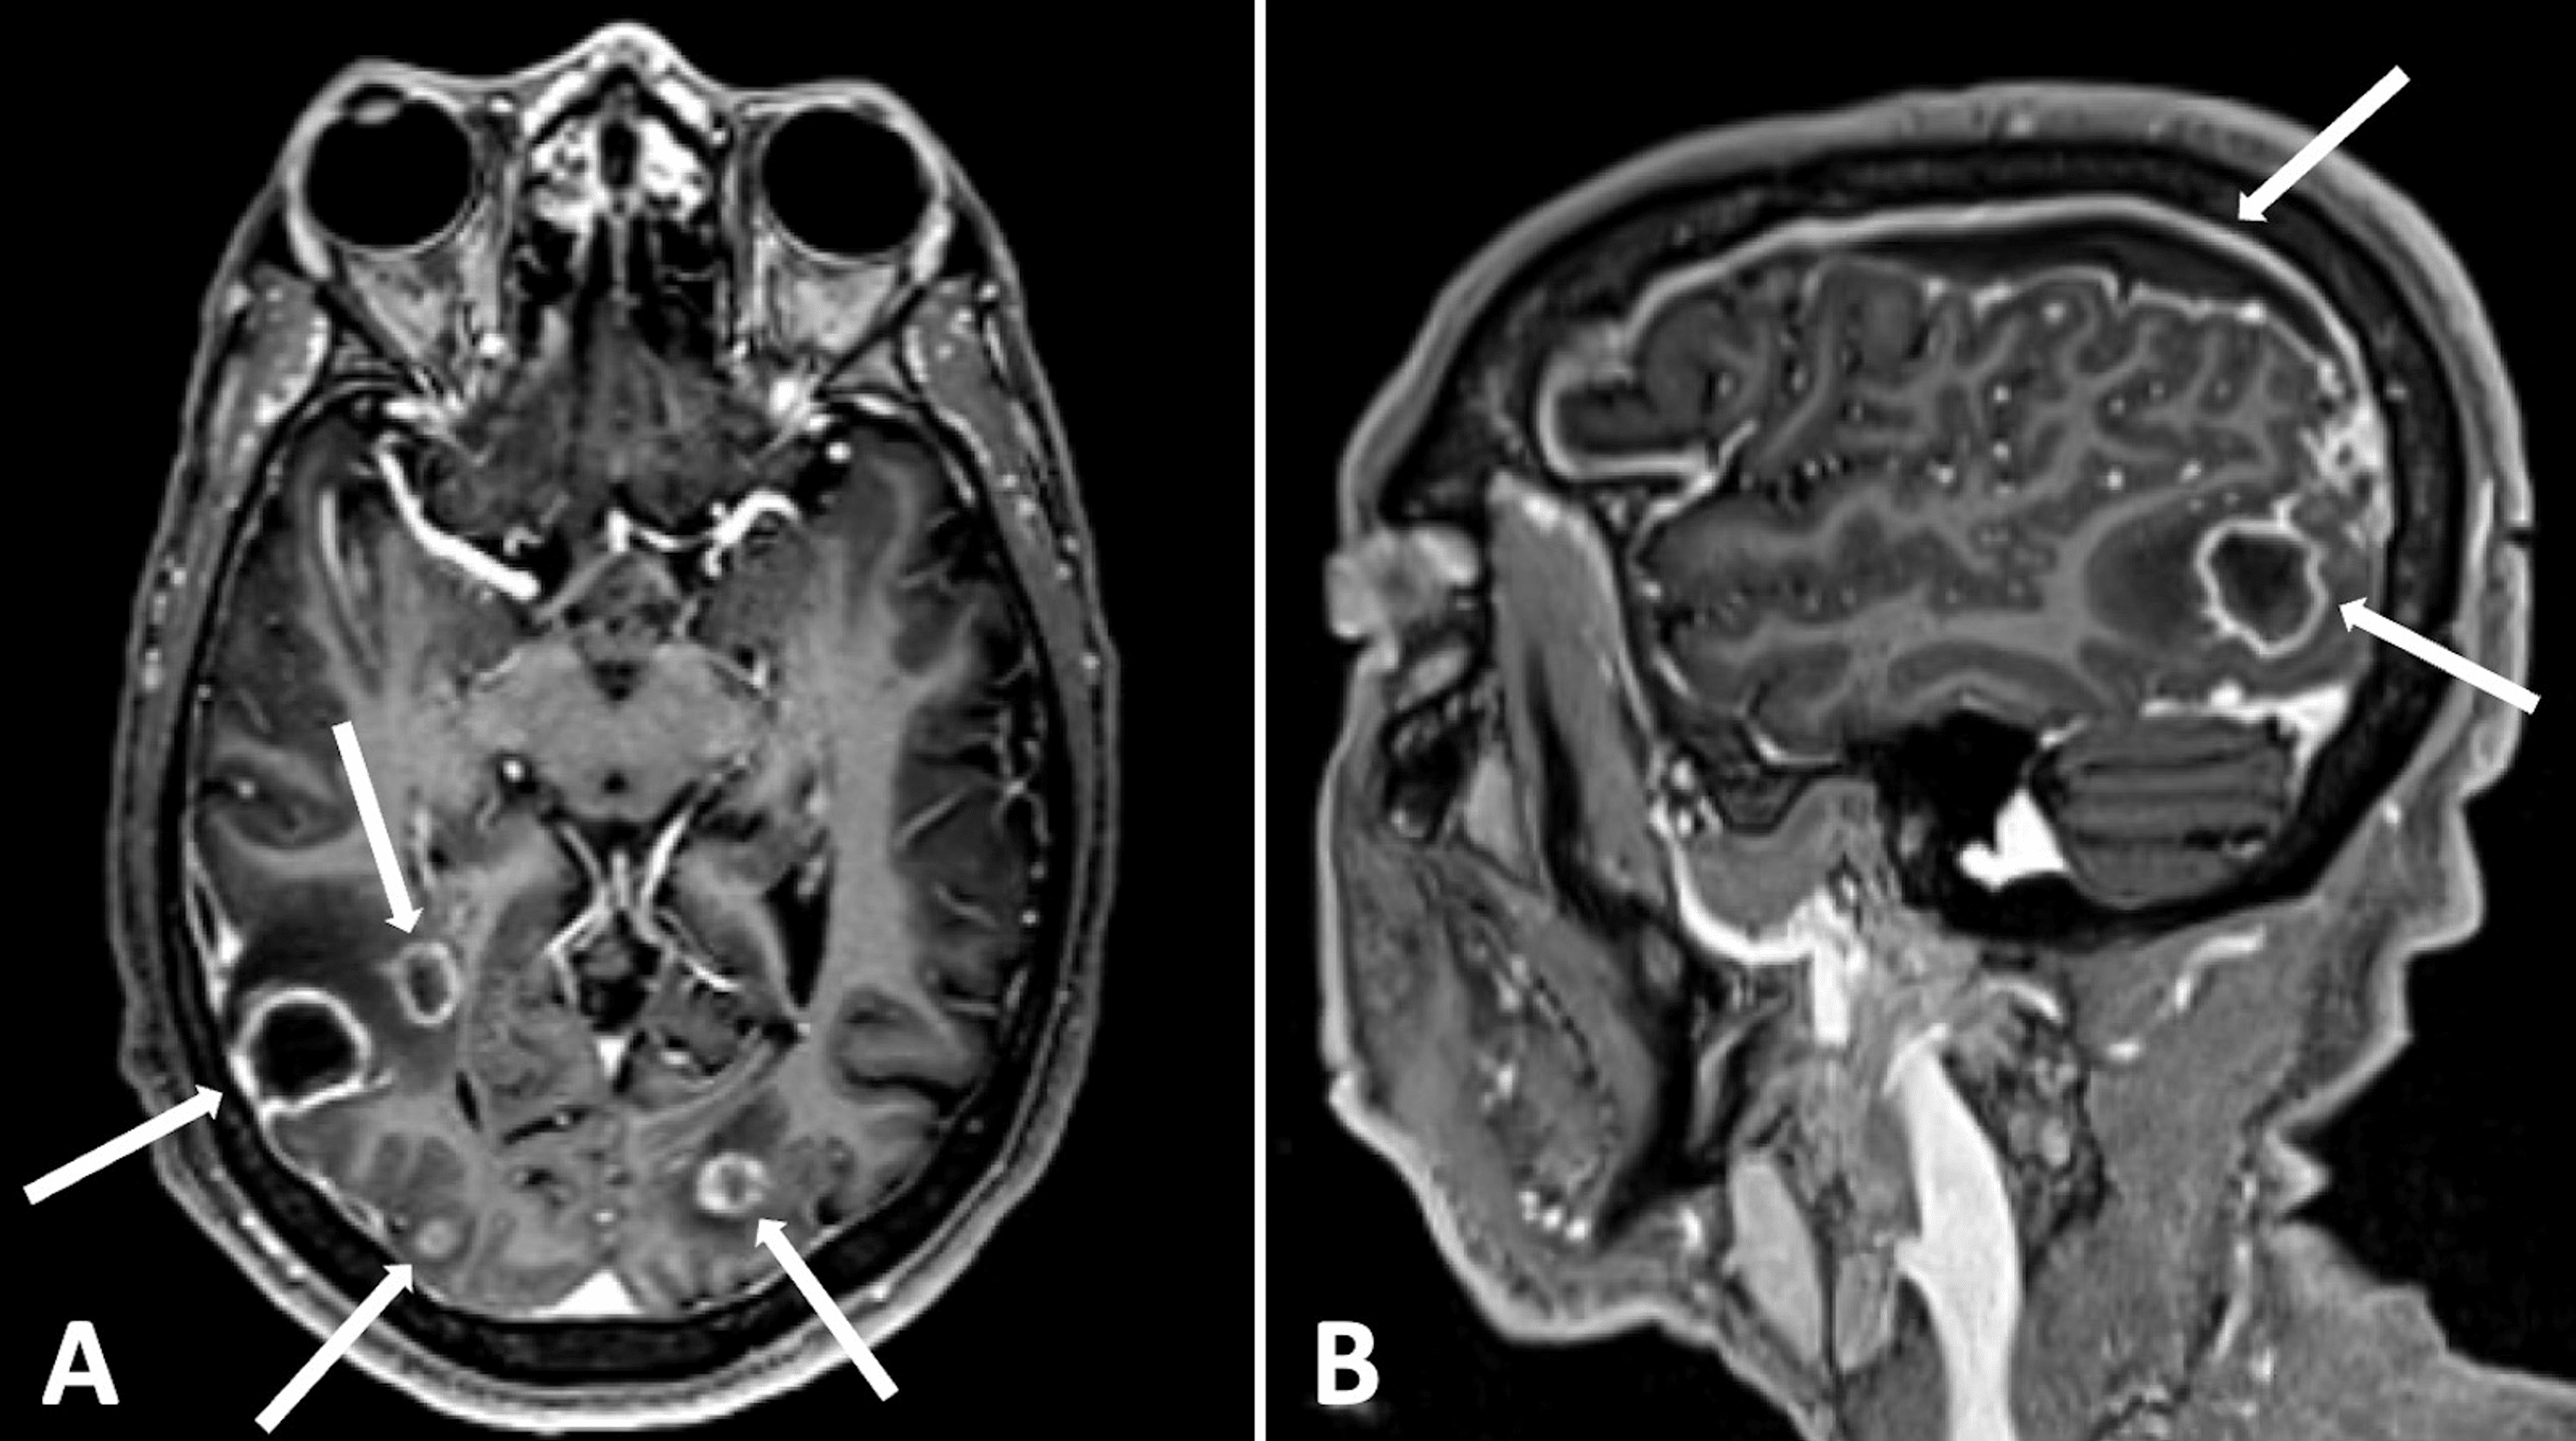

Multiple ringenhancing lesions in a patient with toxoplasmosis are Ring Enhancement In Brain They are most commonly found either subcortical or deeper in the hemisphere (fig. The differential for peripheral or ring enhancing cerebral lesions includes: Magnetic resonance imaging (mri) of the brain showed no evidence of infarction, but the most notable finding was a focus of altered signal with ring enhancement. What are ring enhancing lesions? Ring Enhancement In Brain.